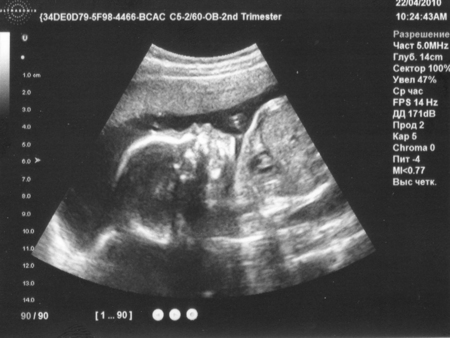

Еще нам в прошлый раз дали нашу фотку (вторую!) На прошлом узи врач забыла отдать. Нам тут 23 недельки.

Вот не пойму. На лице первая выпуклость - это носик, а вторая? губка? губастенькая?)))

Бедра были 88, сейчас 95!!! Вообще все как-то округлилось...:)На узи точно губки :) верхняя пухленькая такая :))